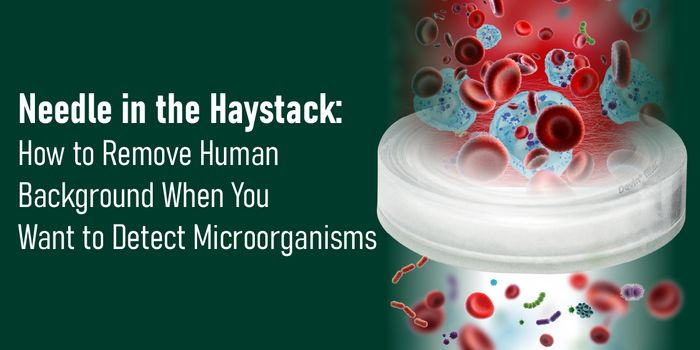

DEC 14, 2020Clinical & Molecular DXHuman sample identification is an essential element of many research projects employing human cells, tissues, or mixture ...